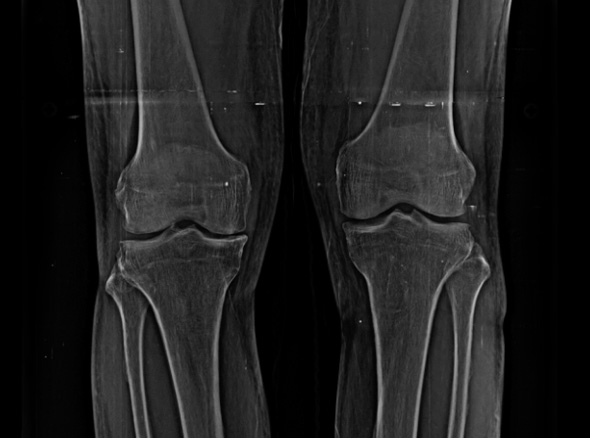

퇴행성관절염은 치료의 시기가 매우 중요합니다.

한번 진행이 시작되면 피하기가 어려워 치료가 빠를수록 진행을 최대한 늦출 수 있습니다.

인공관절 수술은 진행이 악화되어 더 이상 약물로 치료할 수 없을 때 시행하는 최후의 방법입니다.

초기에는 수술이 아닌 비수술 치료만으로 생활에 불편함이 없도록

통증을 완화시키고 증상을 충분히 완화시킬 수 있습니다.

중기에는 비수술치료를 진행하고, 증상이 악화되는 경우 정상 조직을 최대한 보존하고 병변부위만 선택적으로 수술하는 관절내시경을 진행하게 됩니다.